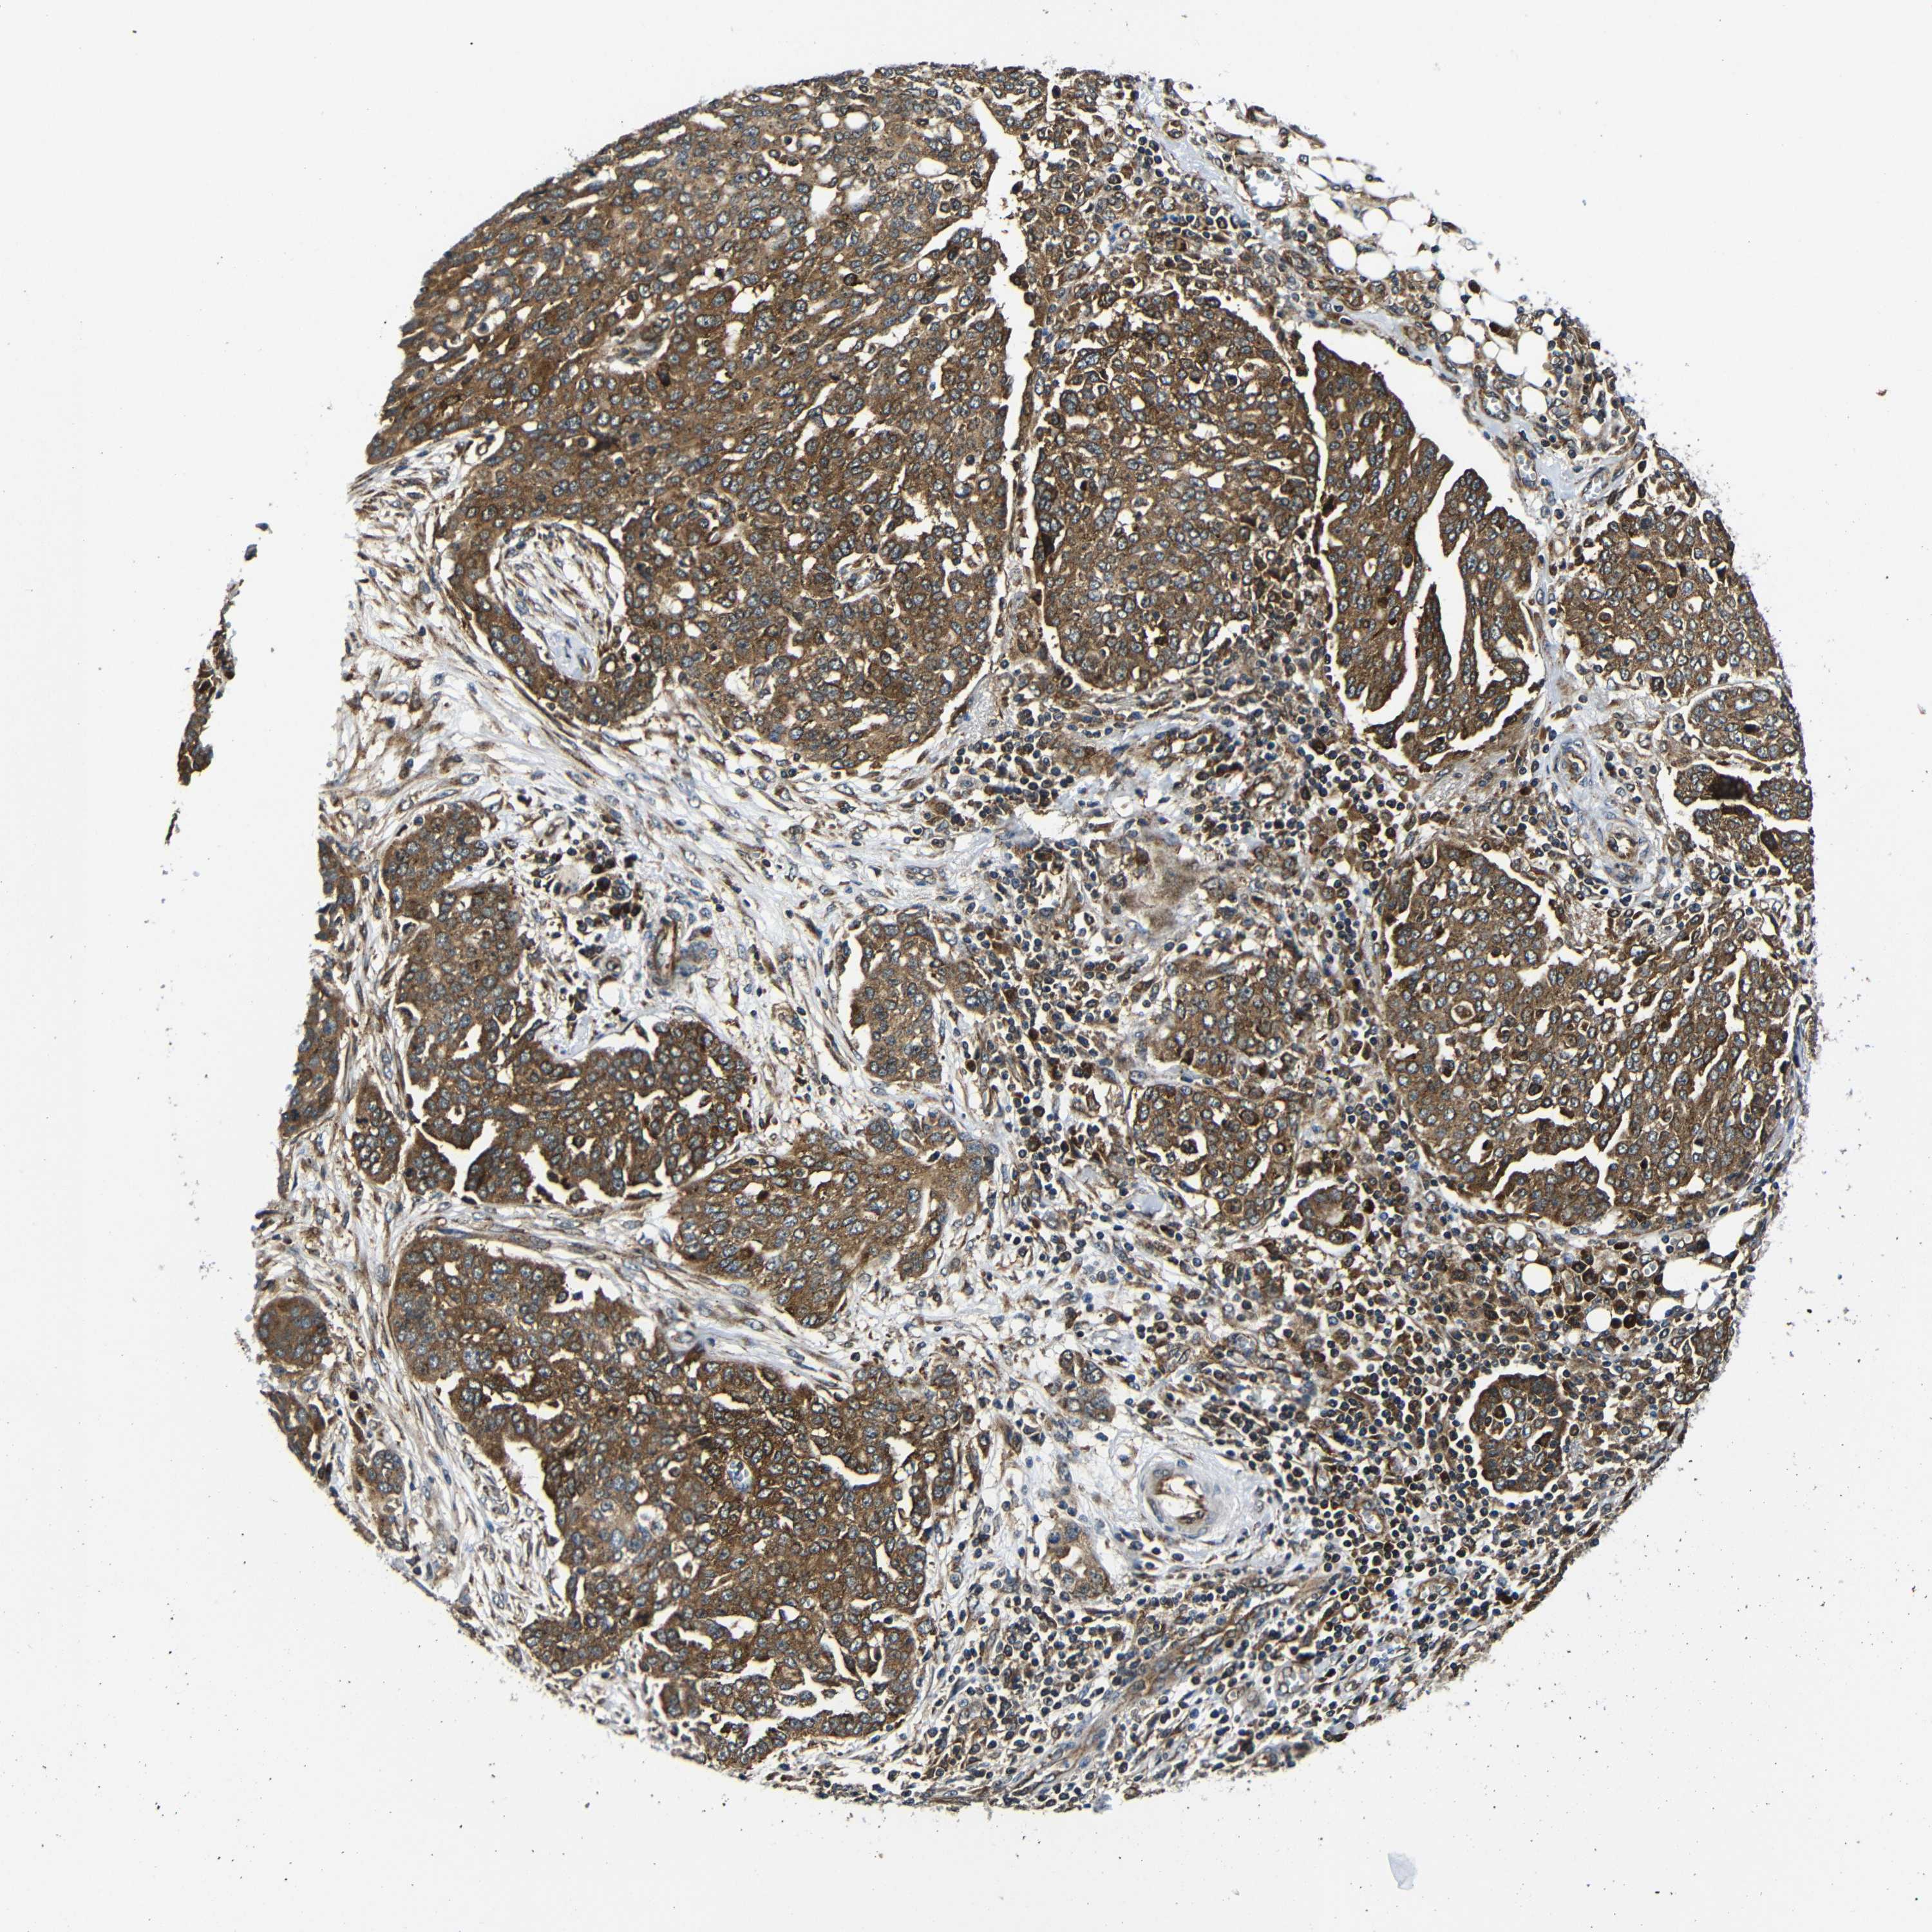

OVARIAN CANCER - Protein expressioni

A mouse-over function shows sample information and annotation data. Click on an image to view it in a full screen mode. Samples can be filtered based on level of antibody staining by selecting one or several of the following categories: high, medium, low and not detected. The assay and annotation is described here.

Note that samples used for immunohistochemistry by the Human Protein Atlas do not correspond to samples in the TCGA dataset.

Antibody stainingi

Antibody staining in the annotated cell types in the current human tissue is reported as not detected, low, medium, or high, based on conventional immunohistochemistry profiling in selected tissues. This score is based on the combination of the staining intensity and fraction of stained cells.

Each image is clickable and will lead to virtual microscopy that enables deeper exploration of all samples and also displays staining intensity scores, fraction scores and subcellular localization as well as patient and tissue information for each sample.

Antibody CAB012476

Staining

High

Medium

Low

Not detected

Intensity

Strong

Moderate

Weak

Negative

Quantity

>75%

75%-25%

<25%

None

Location

Nuclear

Cytoplasmic/membranous

Cytoplasmic/membranous,nuclear

Cystadenocarcinoma, serous, NOS

Carcinoma, endometroid

Cystadenocarcinoma, mucinous, NOS

Carcinoma, NOS